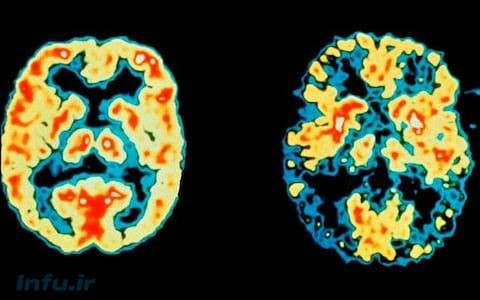

برای اولین بار، ژن آلزایمر در سلولهای مغز انسان خنثی میشود!

برای اولین بار، دانشمندان، پس از خنثی کردن مهم ترین ژن مسئول بیماری آلزایمر، مدعی کسب موفقیت در مبارزه با این بیماری شدند.